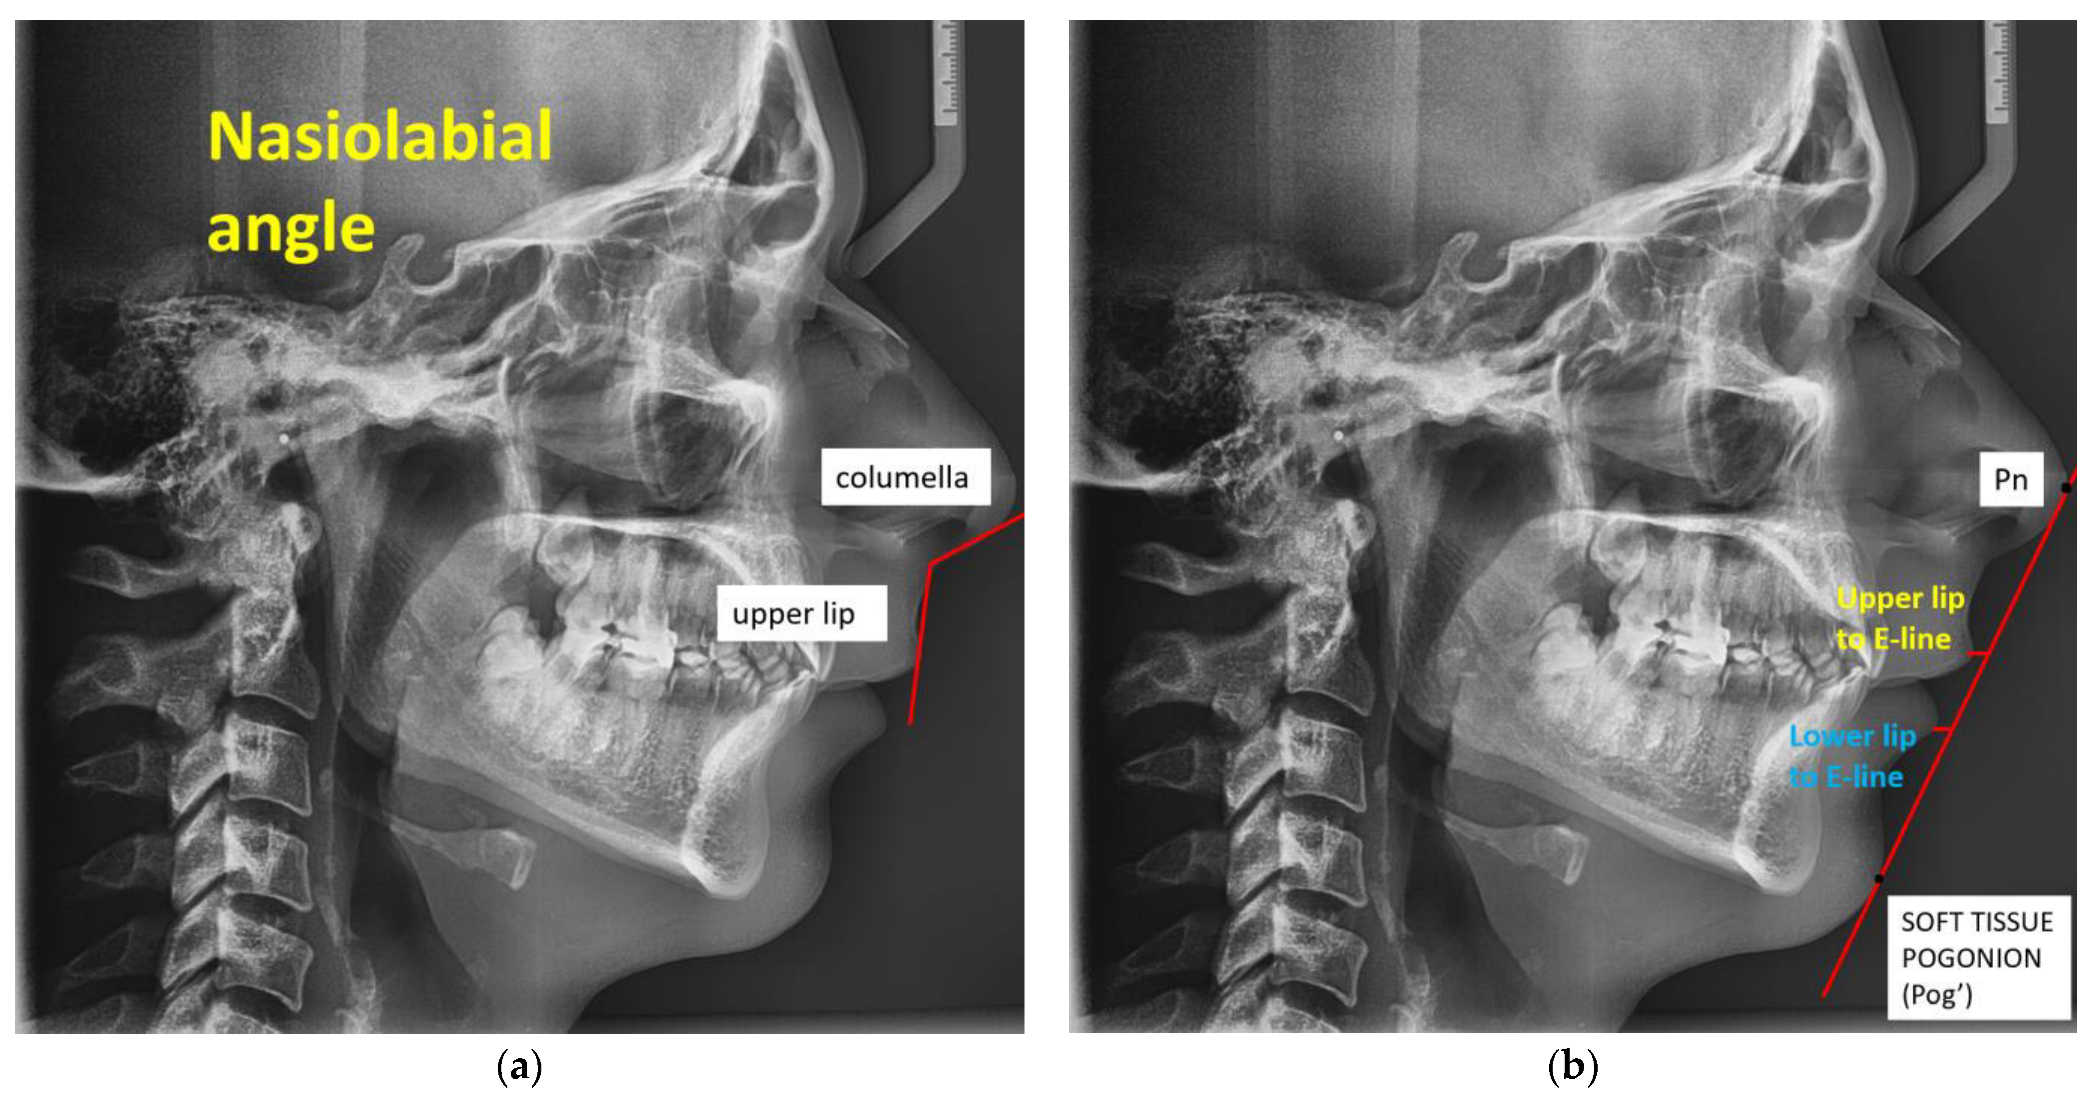

2.1.1. Digital Lateral Cephalometric Measurements and Protocol